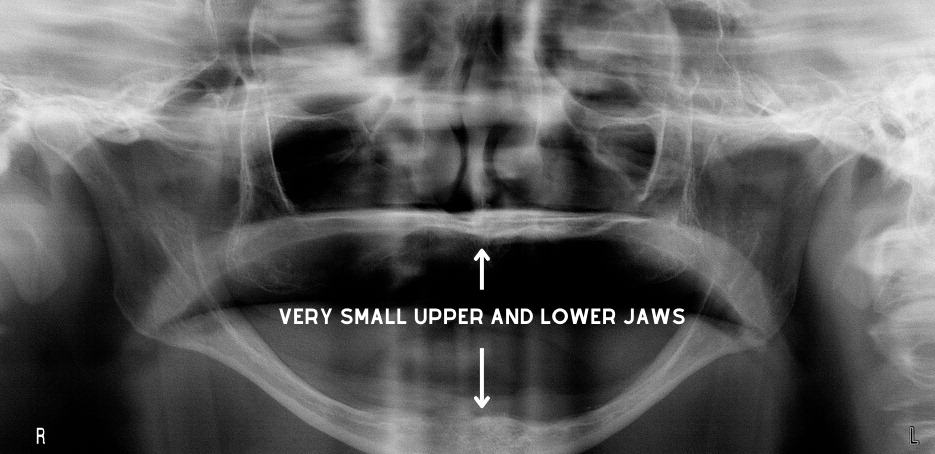

Shrinking Jaws: The jaws exist to hold natural teeth in place. Once teeth are gone, the body will not maintain the jaws. Bone will slowly disappear. The upper jaw residual ridge recedes posteriorly while the lower residual ridge moves anteriorly. Relining the denture base periodically helps keep the dentures fitting and functioning properly.

Eventually, patients will appear as if their lower jaw juts forward. The lower jaw (mandible) usually becomes so atrophic (small) that the lower denture cannot stay in place and becomes useless. I see this in most of my elderly patients. Implants can be a great solution, but they usually have a fixed income and can't afford the treatment.